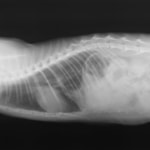

術後レントゲン

腹部臓器が腹腔内に戻り、腹部と胸部の境界および心臓や肺の陰影が明瞭に見えるようになりました。